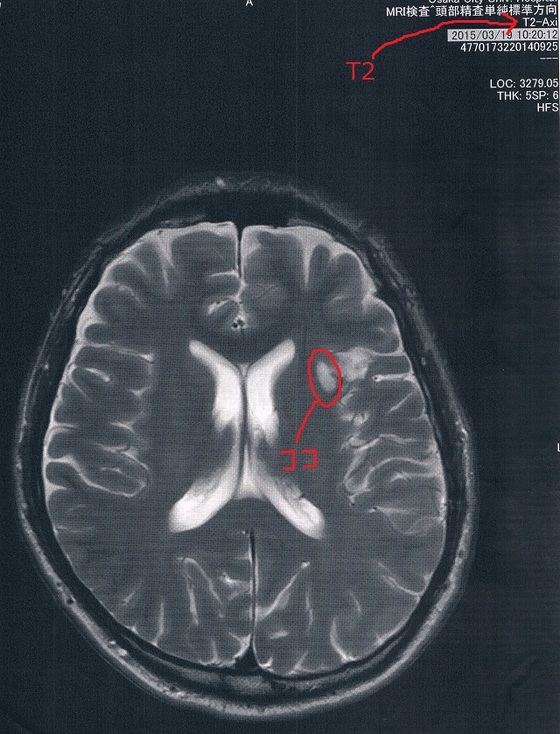

2015/3/19(手術後9か月)のMRI画像

今回もらった画像は前回とは画像強調が異なっているので白黒が反転しているところがある。

が、問題の腫瘍の部分は変化が無いので問題なし!

(興味ある人はFLAIRとT2で検索すると、MRIに詳しくなれます。)